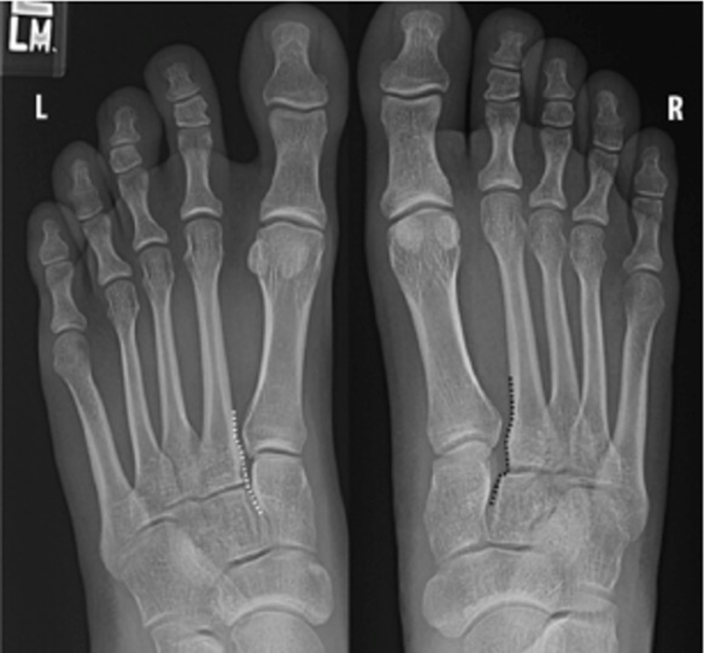

Bilateral plain radiographs show normal alignment of C2-M2 on the left foot (dotted white line), and misalignment of C2-M2 on the right foot (dotted black line). Normally, there should be perfect continuity between the medial cortex of M2 and C2 (Figure 14).